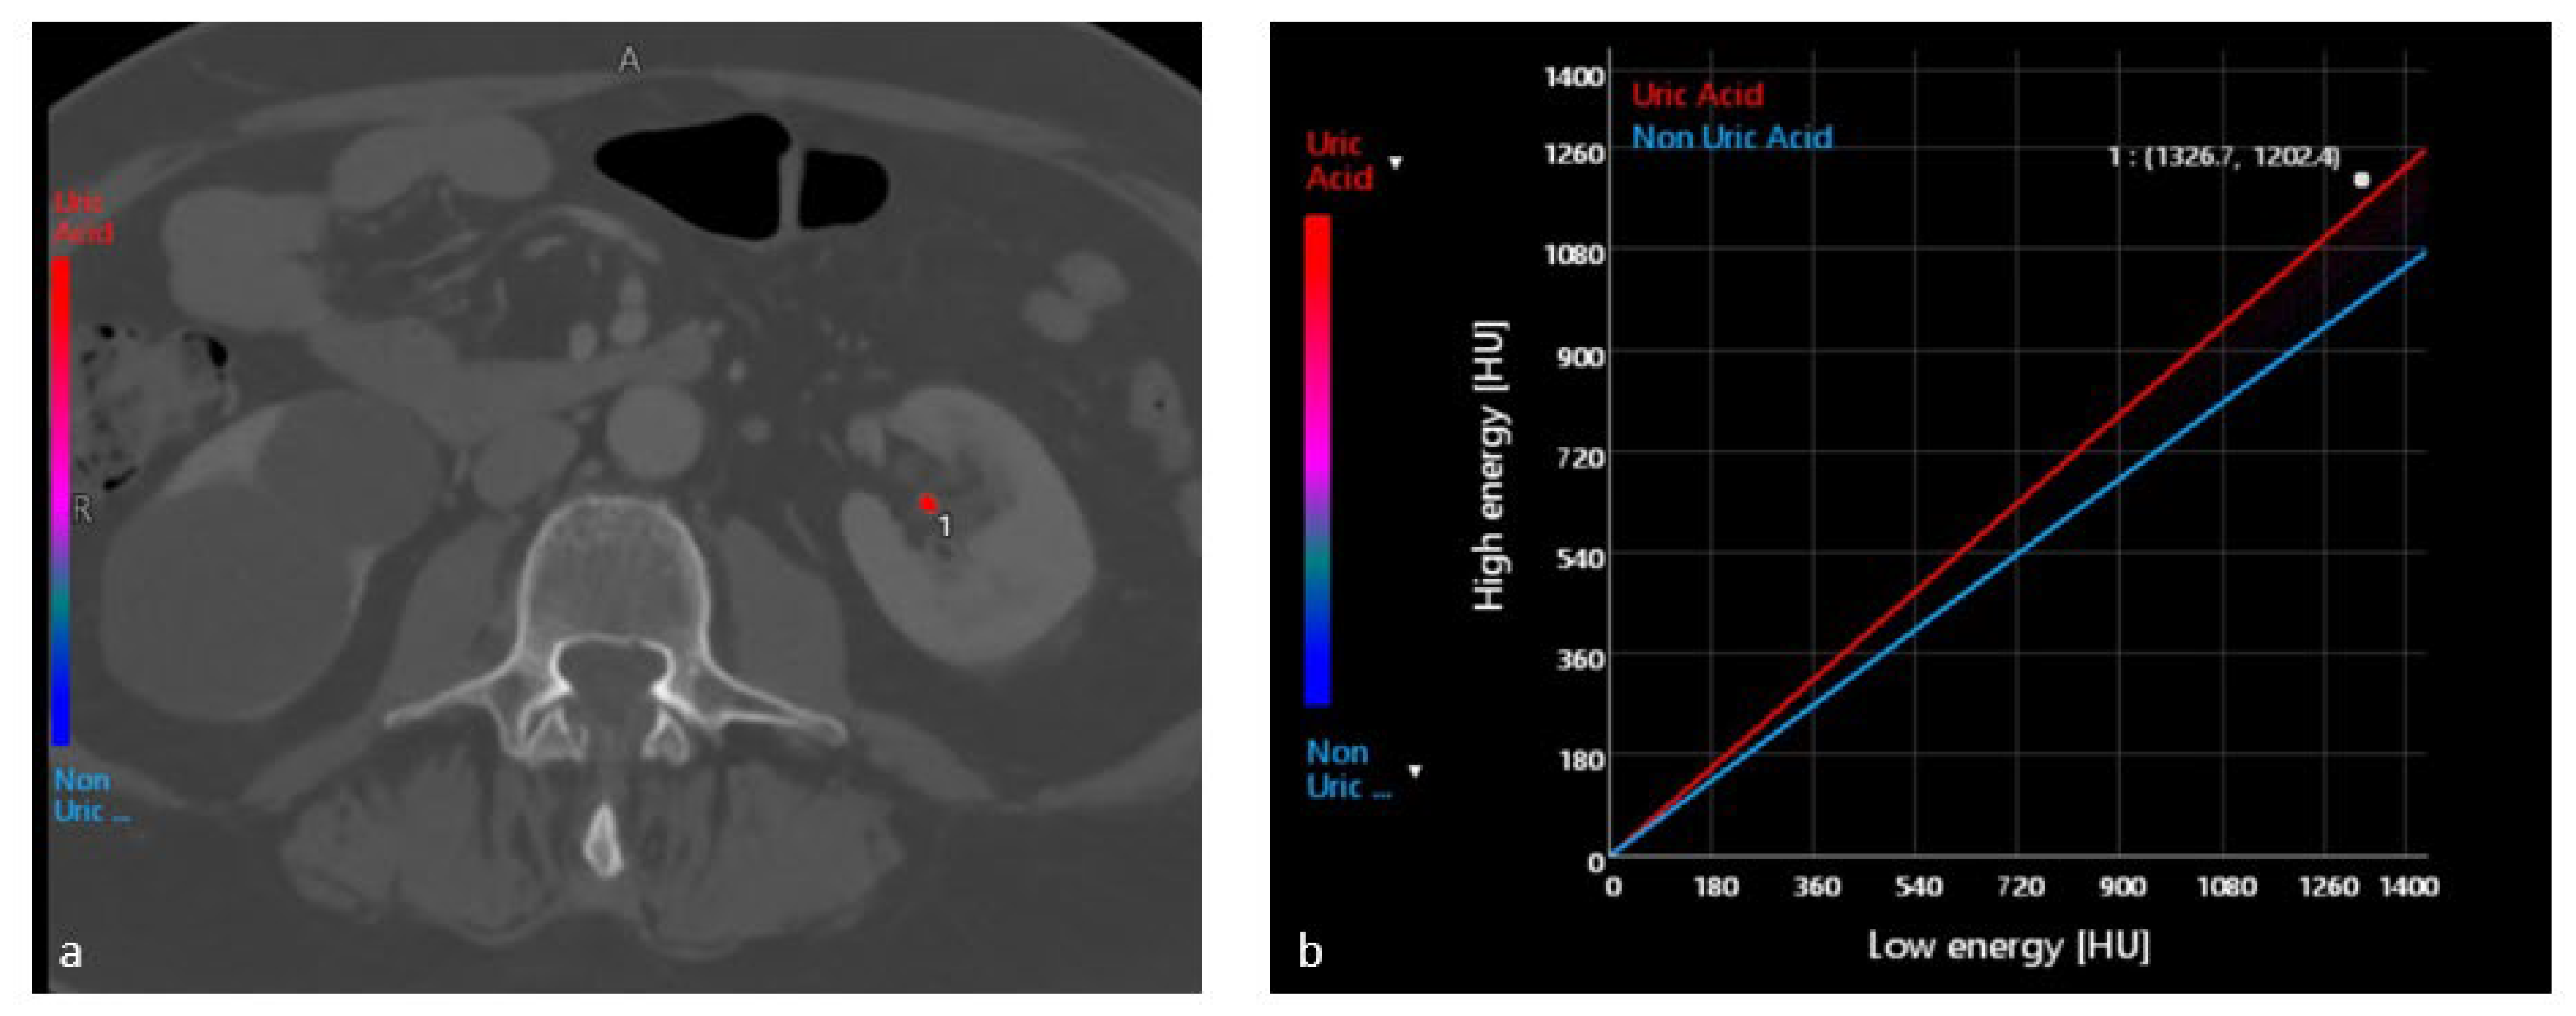

4.1. Characterization of Urinary Stones

- Lombardo, F.; Bonatti, M.; Zamboni, G.A.; Avesani, G.; Oberhofer, N.; Bonelli, M.; Pycha, A.; Mucelli, R.P.; Bonatti, G. Uric Acid versus Non-Uric Acid Renal Stones: In Vivo Differentiation with Spectral CT. Clin. Radiol. 2017, 72, 490–496. [Google Scholar] [CrossRef]

- Bonatti, M.; Lombardo, F.; Zamboni, G.A.; Pernter, P.; Pycha, A.; Mucelli, R.P.; Bonatti, G. Renal Stones Composition in vivo Determination: Comparison between 100/Sn140 KV Dual-Energy CT and 120 KV Single-Energy CT. Urolithiasis 2017, 45, 255–261. [Google Scholar] [CrossRef]